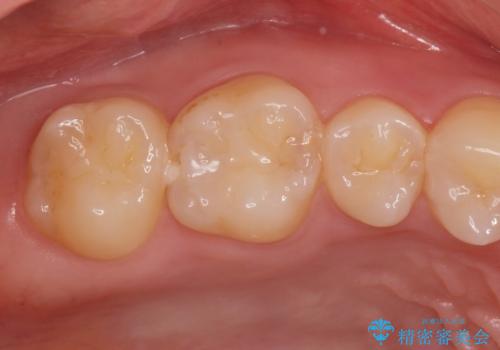

コンタクトカリエスの治療。(e-maxインレー)

- 歯が染みるとの事で来院。歯と歯の間にカリエス(虫歯)が出来ていて穴が空いていました。

拡大鏡下で虫歯を全て取り除き、e-maxインレーで治療を行いました。

適合の良い詰め物が入りました。